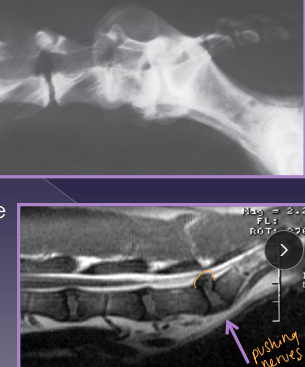

Lumbosacral Disease (Cauda Equina Syndrome)

Et: L7-S1/3 → spinal cord stops @ L5-6

Degenerative: disc protrusion, lig hypertrophy, facet hypertrophy, spondylosis, instability

Dt: rads (spondylosis, narrowed disc), CT, MRI(best)